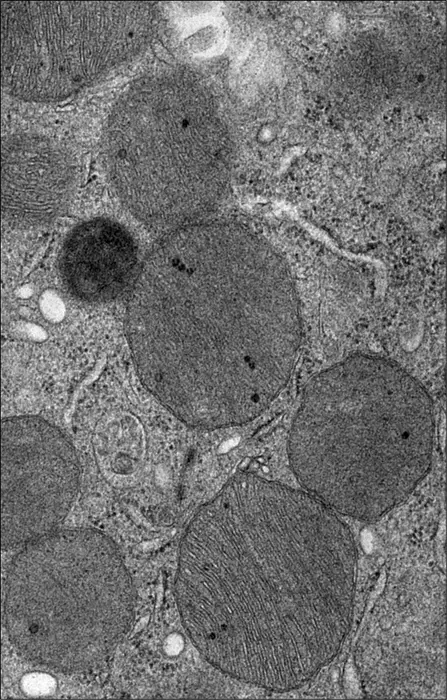

Electron microscope image of badly damaged mitochondria from a kidney with AKI.

Rebekah Nicholson and Linda Nikolova